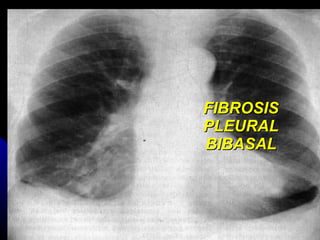

FIBROSIS PLEURAL BIBASAL